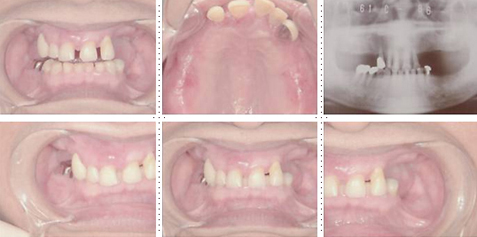

症例3

73才 男性

上顎2本、下顎1本だけ歯が残り、入れ歯を使っておりますが、痛みがありよく噛めない状態。

上顎1本の歯だけを残し、インプラント8本埋入。下顎は歯を抜き、インプラント7本埋入。上下顎とも、セラミック(MB)クラウンをセット。仕事・生活ともに活力が出て、新しい人生が始まったようであると喜んでいただきました。